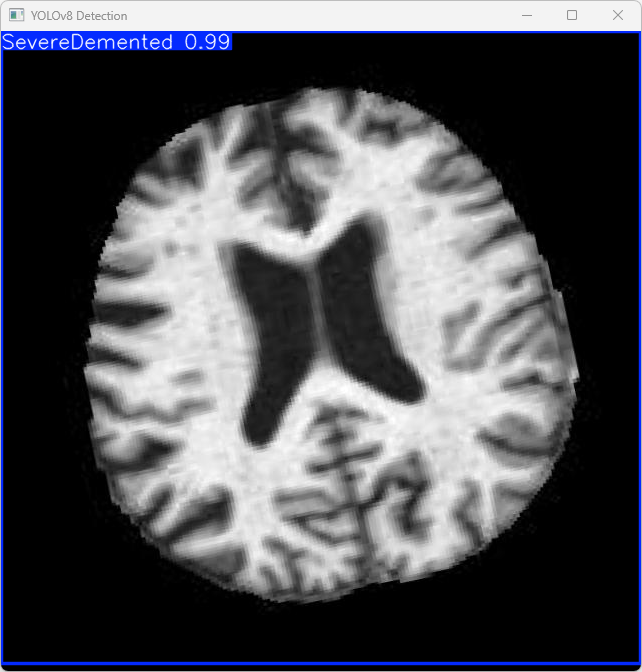

4.检测结果识别

模型训练完成后,我们可以得到一个最佳的训练结果模型best.pt文件,在runs/train/weights目录下。我们可以使用该文件进行后续的推理检测。

imgTest.py 图片检测代码如下:

此代码的功能是加载一个预训练的YOLOv8模型,对指定的图片进行目标检测,并将检测结果显示出来。

执行imgTest.py代码后,会将执行的结果直接标注在图片上,结果如下:

这段输出是基于YOLOv8模型对图片“imagetest.jpg”进行检测的结果,具体内容如下:

图像信息:

(1)处理的图像路径为:TestFiles/imagetest.jpg。

(2)图像尺寸为 640×640 像素。

检测结果:

(1)模型在该图片上检测到 1 个严重痴呆(”1 SevereDemented”)

处理速度:

(1)预处理时间: 14.4 毫秒

(2)推理时间: 5.0 毫秒

(3)后处理时间: 168.1 毫秒

模型在处理图片时非常高效,成功检测出 1 个看屏幕实例,并将结果保存到了指定目录。